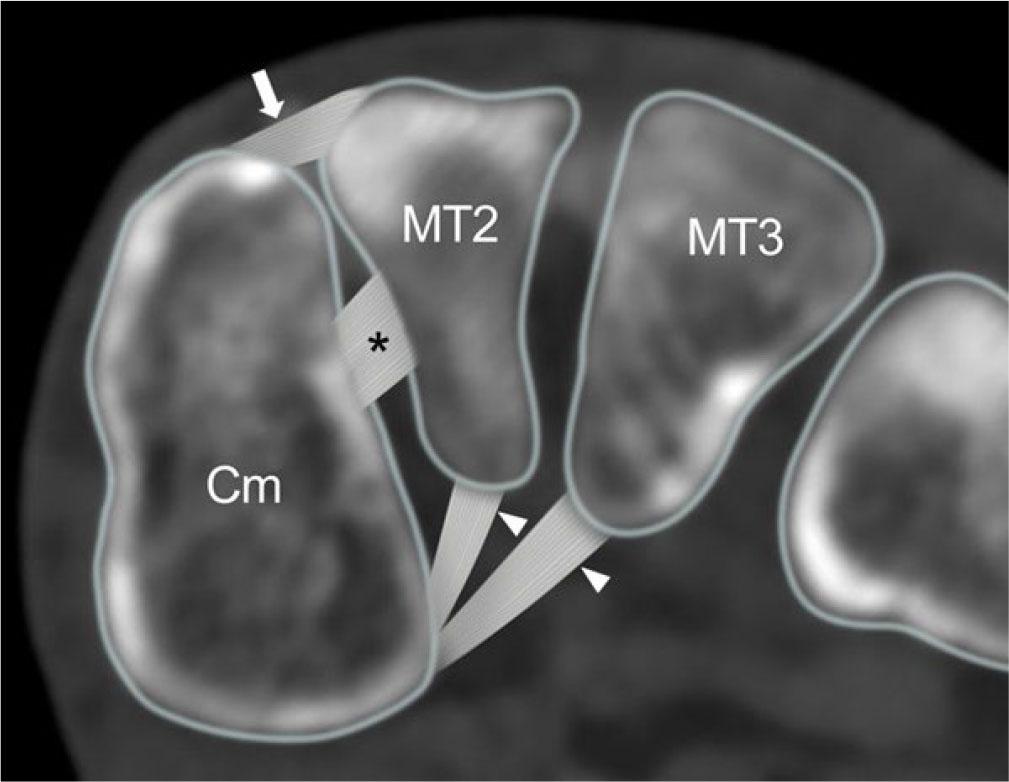

Lisfranc trauma ranges from ligamentous injury to complex fracture-dislocations. It may occur acutely, following high-speed injury, or insidiously, as in diabetic midfoot osteoarthropathy. The Lisfranc ligament complex has three components, with the interosseous component being the strongest and the dorsal component being the weakest (Fig. 7, Fig. 8)(7). The strong intercuneiform ligament between the medial and intermediate cuneiform bones also indirectly helps stabilize the Lisfranc articulation(7). In patients undergoing surgery for suspected Lisfranc injury, the interosseous Lisfranc ligament was torn in 100%, the dorsal component was torn in 75%, and the intercuneiform ligament was torn in 25%(7). Ligament injury can be isolated or associated with severe fracture-dislocation. Conventional foot radiographs are the first-line imaging modality. In patients with high energy trauma, the diagnosis is usually obvious, and CT will help with surgical planning(8). In patients with low-energy injury, bilateral weight-bearing radiographs are helpful at detecting subtle subluxation, though obtaining standing radiographs is often impractical in the acute setting. CT will reveal nondisplaced fractures and subtle subluxation that may be overlooked radiographically (Fig. 9)(8). Weight-bearing CT is also feasible(9). On ultrasound, only the dorsal component of the Lisfranc ligament complex can be reliably seen. Both feet should be compared. Ultrasound signs of a Lisfranc injury include a thickened or absent dorsal ligament, with or without a medial cuneiform-2nd metatarsal distance of >2.5 mm which may further widen on weight-bearing(10). A normal dorsal Lisfranc ligament does not exclude additional ligament injury(8). MRI reliably demonstrates all of the Lisfranc and inter-cuneiform ligaments and is the non-operative gold standard for diagnosing ligament injury (Fig. 8)(8).

Fig. 7.

Schematic diagram of Lisfranc ligament complex shows dorsal (arrow), interosseous (*) and plantar (arrowheads) components of Lisfranc ligament. Cm, medial cuneiform, MT2, second metatarsal base, MT3, 3rd metatarsal base